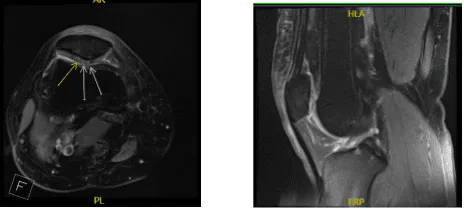

Se realizó una resonancia magnética que mostró una lesión osteocondral en la articulación patelofemoral. No tuvo alivio con tratamiento no quirúrgico. Hablamos sobre opciones de tratamiento y manejo quirúrgico quirúrgico.

Resonancia magnética de rodilla derecha sin contraste